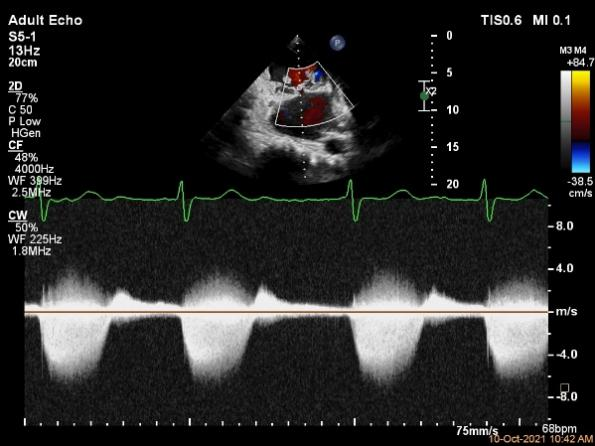

术中及术后即刻超声评估

肺静脉血流频谱恢复正向